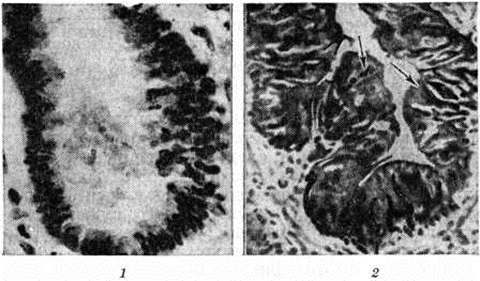

Период спазматического кашля изучен лучше. Причиной смерти детей в этом периоде в большинстве случаев является пневмония; редко смерть наступает во время кашлевых пароксизмов от асфиксии вследствие ларингоспазма либо от расстройства мозгового кровообращения. Морфологически изменения включают изменения, вызванные коклюшной палочкой и её токсином, изменения в органах дыхания, обусловленные вторичной флорой, а также расстройства кровообращения и последствия этих расстройств. Первые два типа изменений разграничить довольно трудно. Считается, что чисто «коклюшные» изменения в гортани, трахее и бронхах ограничиваются серозно-катаральным воспалением (смотри полный свод знаний). Слизистая оболочка дыхательных путей выглядит в той или иной степени гиперемированной, покрыта слизью. Эпителий на всем протяжении сохраняет структуру многорядного цилиндрического, с большим количеством бокаловидных клеток. Наибольшие изменения имеются в гортани и особенно в голосовых складках. Здесь наблюдается пролиферация эпителиальных клеток с утолщением эпителиального пласта, вакуольная дистрофия (смотри полный свод знаний) и слущивание отдельных клеток, отёк подслизистой основы с незначительными гистиоцитарными инфильтратами, местами незначительные скопления серозного экссудата между эпителиальными клетками. Базальная мембрана в области голосовых складок, в меньшей степени в области трахеи, выглядит резко набухшей, как бы расплавленной, сливается с подлежащей отёчной тканью, отодвигая и истончая эпителиальный пласт. Обнаруживаются морфологический изменения в рецепторном нервном аппарате гортани: удлинение терминальных нитей, повышенная аргирофилия концевых нитей в эпителиальном пласте и в подлежащей соединительной ткани без разрушения нервных окончаний. Считают, что эти изменения обусловлены состоянием длительного раздражения нервного аппарата гортани под влиянием токсина возбудителя Коклюш

В период спазматического кашля при неосложнённом Коклюш многообразные изменения обнаруживаются в лёгких. Одни из этих изменений являются проявлением функциональный расстройств, обусловленных повторяющимся спазматическим состоянием дыхательных путей, возможно, в связи с действием коклюшного токсина на нервный аппарат самого лёгкого, — эмфизема смотри полный свод знаний Эмфизема лёгких), ателектазы (смотри полный свод знаний), спастическое состояние бронхов (рисунок 1). Другие изменения по сути своей являются воспалительными. Анализируя большой секционный материал и проведя сопоставления с клиникой, бактериологические и бактериоскопическими исследованиями, А. П. Тарасова и А. Д. Швалко (1966) пришли к выводу о возможности возникновения мелкоочаговых «коклюшных» пневмоний. Распространение процесса идёт бронхогенным путём с вовлечением бронхиол и респираторных отделов лёгкого. В бронхах и альвеолах наблюдается серозное воспаление, в экссудате обнаруживается небольшое количество лейкоцитов и макрофагов. В бронхах экссудат содержит слизь, в стенке бронхов наблюдается умеренная пролиферация соединительнотканных клеток. В дальнейшем клетки бронхиального и альвеолярного эпителия подвергаются некрозу. Представления о роли коклюшной палочки как первичного причинного фактора, обусловливающего развитие пневмонии, придерживается также А. В. Цинзерлинг (1970). Ряд исследователей также считают коклюшную палочку причиной развития патологический процесса в альвеолах (пневмококлюш), однако не называют эти изменения пневмонией, а обозначают терминами «пневмопатия генерализованная» (пневмококлюш альвеолярный или гидроальвеолит диффузный) и «пневмококлюш очаговый». При попытке экспериментального воспроизведения Коклюш у мышей путём аэрозольного и интраназального заражения животных была получена очаговая фибринозно-гнойная пневмония с большим количеством коклюшных палочек в экссудате.